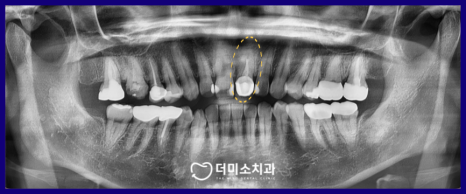

정밀한 검사를 위해

파노라마 사진과 X-ray 사진을

촬영해 보았더니

신경치료 후 채워 넣는 치과 재료가

뿌리 끝까지 꼼꼼하게 채워지지 않은

불완전 근관치료 상태인 것을

확인할 수 있었는데요.

이 경우 재신경치료가

필요한 상황이었습니다.